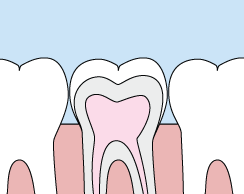

Crowns

Crowns are a cosmetic restoration used to improve your tooth’s shape or to strengthen a tooth. Crowns are most often used for teeth that are broken, worn, or have portions destroyed by tooth decay.

A crown is a "cap" cemented onto an existing tooth that fully covers the portion of your tooth above the gum line. In effect, the crown becomes your tooth’s new outer surface. Crowns can be made of porcelain, metal, or both. Porcelain crowns are most often preferred because they mimic the translucency of natural teeth and are very strong.

Crowns or onlays (partial crowns) are needed when there is insufficient tooth strength remaining to hold a filling. Unlike fillings, which apply the restorative material directly into your mouth, a crown is fabricated away from your mouth. Your crown is created in a lab from your unique tooth impression, which allows a dental laboratory technician to examine all aspects of your bite and jaw movements. Your crown is then sculpted just for you so that your bite and jaw movements function normally once the crown is placed.